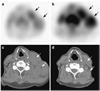

The success of cancer therapy can be difficult to predict, as its efficacy is often predicated upon characteristics of the cancer, treatment, and individual that are not fully understood or are difficult to ascertain. Monitoring the response of disease to treatment is therefore essential and has traditionally been characterized by changes in tumor volume. However, in many instances, this singular measure is insufficient for predicting treatment effects on patient survival. Molecular imaging allows repeated in vivo measurement of many critical molecular features of neoplasm, such as metabolism, proliferation, angiogenesis, hypoxia, and apoptosis, which can be employed for monitoring therapeutic response. In this review, we examine the current methods for evaluating response to treatment and provide an overview of emerging PET molecular imaging methods that will help guide future cancer therapies.